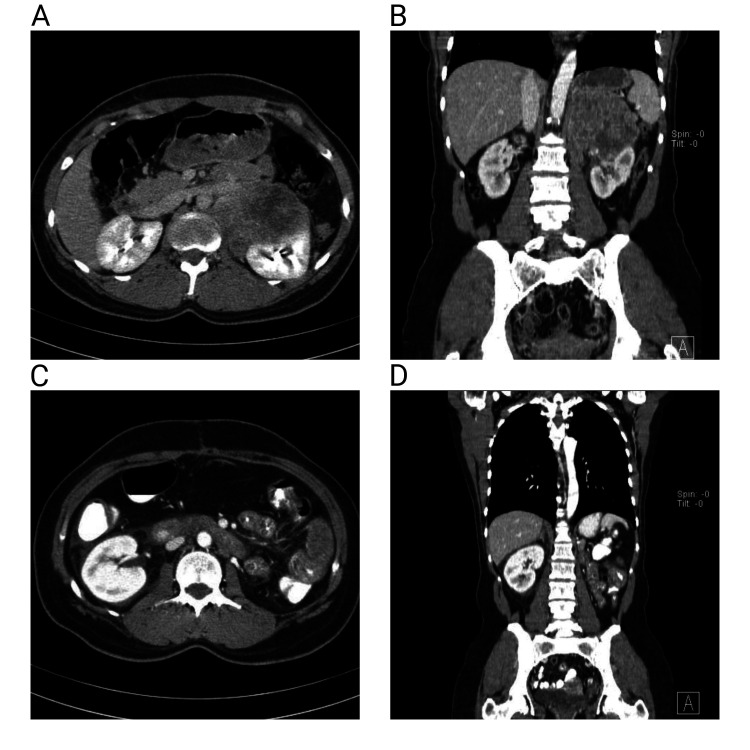

Locally advanced renal cell carcinoma (RCC) presents significant therapeutic challenges, particularly in resource-limited settings with restricted access to new therapies. This report describes a new exploratory multimodal therapeutic approach for a patient with locally advanced clear cell RCC (ccRCC) with adrenal and lymph node metastases. A 45-year-old woman presented with an incidentally discovered 9-cm mass in the left kidney, which was later diagnosed as grade-2 ccRCC with adrenal and lymph node involvement. After radical nephrectomy, a multimodal treatment regimen consisting of sunitinib, pembrolizumab, bevacizumab, sirolimus, and zoledronic acid was initiated. Following eight cycles of treatment, computed tomography imaging and ultrasound showed considerable tumor shrinkage, with residual mass decreasing from 22 × 42 mm to 22 × 18 mm, which constituted a "radiologically complete response." The patient had compensatory hypertrophy of the contralateral kidney with preserved renal function. This case illustrates the potential efficacy of a novel multimodal treatment strategy combining targeted therapies, immunotherapy, and bone-modifying agents in a resource-limited setting. Further research is needed to validate this approach in larger, diverse patient cohorts.